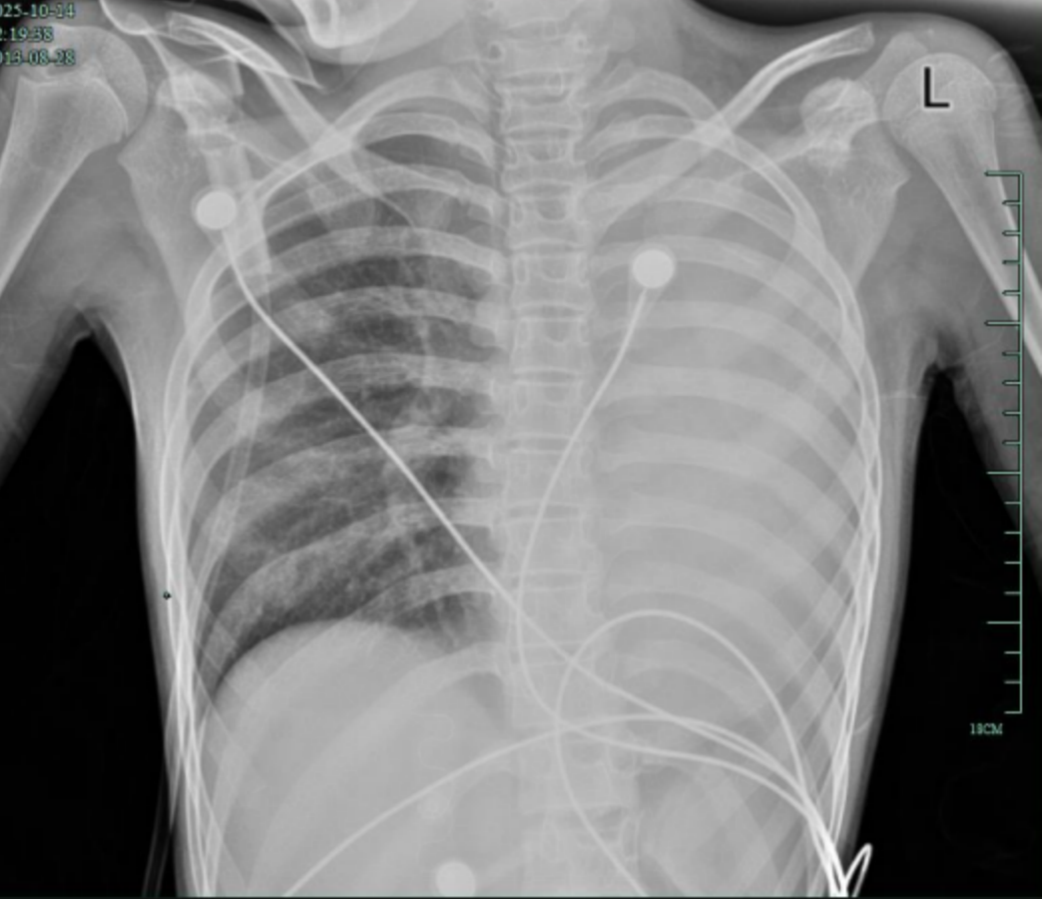

孩子感冒咳嗽看似常见,12岁女孩笑笑(化名)的经历却让人感到后怕——仅发热1天,左肺就变成了“白肺”,呼吸急促到无法平躺,血氧饱和度勉强维持在90%左右,情况十分危急!

治疗前,左肺呈“白肺”状态 医院供图

在浙大四院儿科等多学科团队的努力下,笑笑已经转危为安。不过这次来势汹汹的急症背后,藏着一种容易被忽视的急性重症呼吸道疾病——塑型性支气管炎。